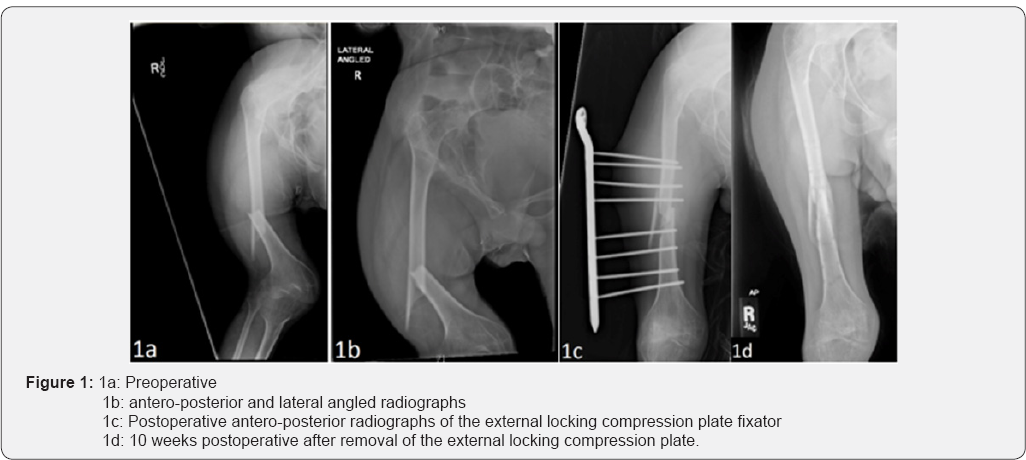

A 22-year old male presented to the emergency department with acute onset of right thigh pain after his caretaker lifted him out of bed. Past medical history included chronic right hip dislocations, MRDD, growth delay, and seizure disorder due to anoxic brain injury. Examination revealed a shortened right lower extremity with tenting of the skin on the lateral aspect of the thigh with significant bruising, without open fracture. Sensation and motor function were unable to be obtained due to patient's non-verbal status and inability to follow commands. Radiographs revealed a displaced distal femoral shaft fracture in a spiral configuration. 5lbs of Bucks traction was placed on the lower right limb until the patient underwent surgery the following day.

Once in the operating room, his right femoral shaft fracture was reduced and held using traction. The plate used was an ITS 9 hole right distal femoral locking plate that was flipped around such that the distal end was now proximal. The plate was placed 2-3cm off the skin, and a plastic spacer of the same thickness was placed in between the skin and the plate. This was done in order to maintain the distance between the skin and the plate. Stab incisions through the skin were made, and eight 4.5mm cortical locking screws were used, four proximal to and four distal to the fracture site respectively (Figure 1c). Care was taken all the while to maintain the reduction and distance from the plate to the skin. Post-operatively, the patient had multiple episodes of hypotension and tachycardia. The patient then stabilized over the next few days, and was discharged from the hospital on postoperative day four. The patient remained non-weight bearing, and received follow up imaging every 2-3 weeks for the next ten weeks. The radiographs showed good callus formation at 9 weeks post-operatively. At ten weeks after the initial surgery, the external locking plate and screws were removed under general anesthesia (Figure 1d). The patient was followed for two more months, healed his fracture fully, and continued to do well.